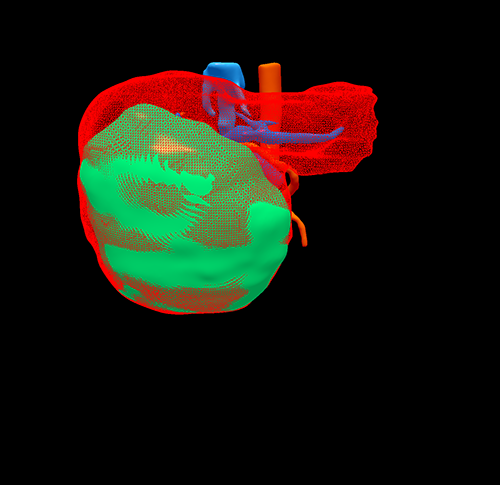

右肝癌---右三肝切除